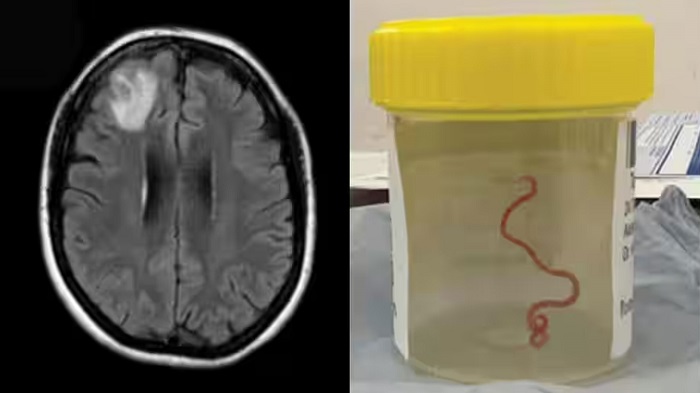

সোমবার (২৮ আগস্ট) দ্য গার্ডিয়ান এক প্রতিবেদন জানিয়েছে, অস্ট্রেলিয়ার ক্যানবেরা হাসপাতালে এক ইংরেজ নারীর ব্রেইনে অপারেশন করে জীবন্ত গোলকৃমি বের করা হয়। ডা. হরি প্রিয়া বান্দি নামে হাসপাতালের এক নিউরোসার্জন রোগীর মস্তিষ্ক থেকে ৮ সেমি দীর্ঘ একটি কৃমিটি বের করেন।

কৃমিটি বের করার পর সহকর্মী সংক্রামক রোগের চিকিৎসক ডা. সঞ্জয় সেনানায়েকেকে ডেকে বিষয়টি জানান ডা. হরি প্রিয়া বান্দি এবং বলেন, ‘আপনি বিশ্বাস করবেন না, আমি এইমাত্র এক নারীর ব্রেইনে কি পেয়েছি।’ তার কথায়, ‘কৃমিটি তখনও জীবন্ত ছিল ও নড়াচড়া করছিল।’

এরপর অবিরাম শুকনো কাশি, জ্বর ও রাতে ঘাম হওয়ার মতো সমস্যাও দেখা দেয়। এই উপসর্গগুলো ছাড়াও ২০২২ সালের দিকে দেখা দেয় স্মৃতিবিভ্রম ও অবসাদ। যার প্রেক্ষিতে স্থানীয় চিকিৎসকরা তাকে ক্যানবেরা হাসপাতালে পাঠান। এখানে তার এমআরআই করা হয়। এতে তার ব্রেইনে অস্বাভাবিক কিছুর উপস্থিতি ধরা পড়ে এবং অপারেশনের প্রয়োজন হয়।

সেনানায়েক বলেন, আমরা তখনই পাঠ্যবই খুলি। ব্রেইনে অনুপ্রবেশ ও রোগ সৃষ্টি করতে পারে এমন সব ধরনের গোলকৃমি সম্পর্কে খোঁজ শুরু করি। কিন্তু কোনো সমাধান না পেয়ে আমরা বাইরের বিশেষজ্ঞের সহযোগিতা নিই। জীবন্ত কৃমিটি সিএসআইআরও-এর একজন বিশেষজ্ঞের কাছে পাঠালে তিনি এক দেখাতেই তা চিনতে পারেন এবং এটির বৈজ্ঞানিক নাম ওফিডাসকারিস রবার্টসি বলে জানা যায়।